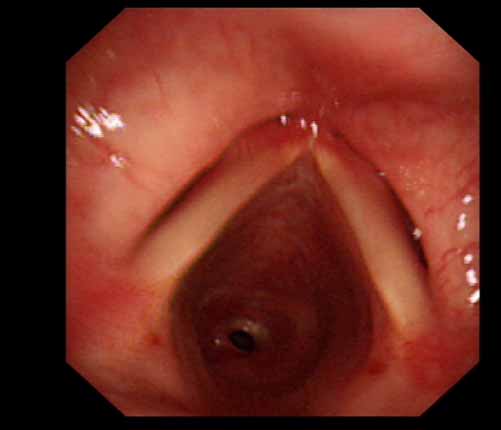

患者李某某,女,45歲,因氣管插管咳嗽、喘憋10天入院。頸部CT檢查示聲門下約20mm處氣管明顯狹窄,狹窄段長約26mm,最窄處直徑約4.4mm。支氣管鏡檢查見聲門下約2cm氣管呈漏斗狀縮窄,直徑約4-5mm,支氣管鏡無法通過。經科室討論,決定行電子支氣管鏡下氣管球囊擴張治療。與患者及家屬充分溝通并經三方見證談話簽署知情同意書后,在患者持續吸氧、局麻下,科主任于世倫主任醫師帶領治療小組為患者實行電子支氣管鏡下氣管球囊擴張術。手術過程順利,出血量很少,術后患者呼吸困難癥狀即可明顯緩解。10天后行二次擴張,患者日常活動無明顯喘憋,二次術后5天出院。

術前聲門下的漏斗樣狹窄口 術中球囊擴張 術后擴張開的氣管管腔